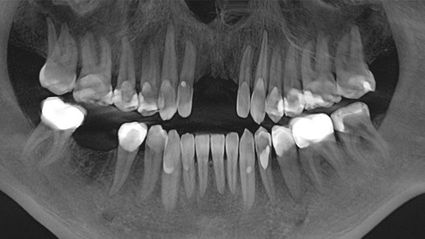

My first visit was in December 16. I had my 4 wisdom teeth cavitations cleaned, 3 more cavitations (from teeth that had been extracted in the summer 16 in the USA) cleaned, and implants placed. I also had a gold crown removed, along with a little metal. This last visit on July 16, we fixed various teeth that had plastic fillings and replaced them with ceramic fillings and crowns. We most importantly extracted 2 teeth that had deep root infections, cleaned cavitations and placed 2 implants. I experienced an almost immediate sigh of relief in my whole body. Then a boost of energy! Here, all the attention is paid to ensuring the patient has the best chance to heal and recover both before, during, and after surgery.